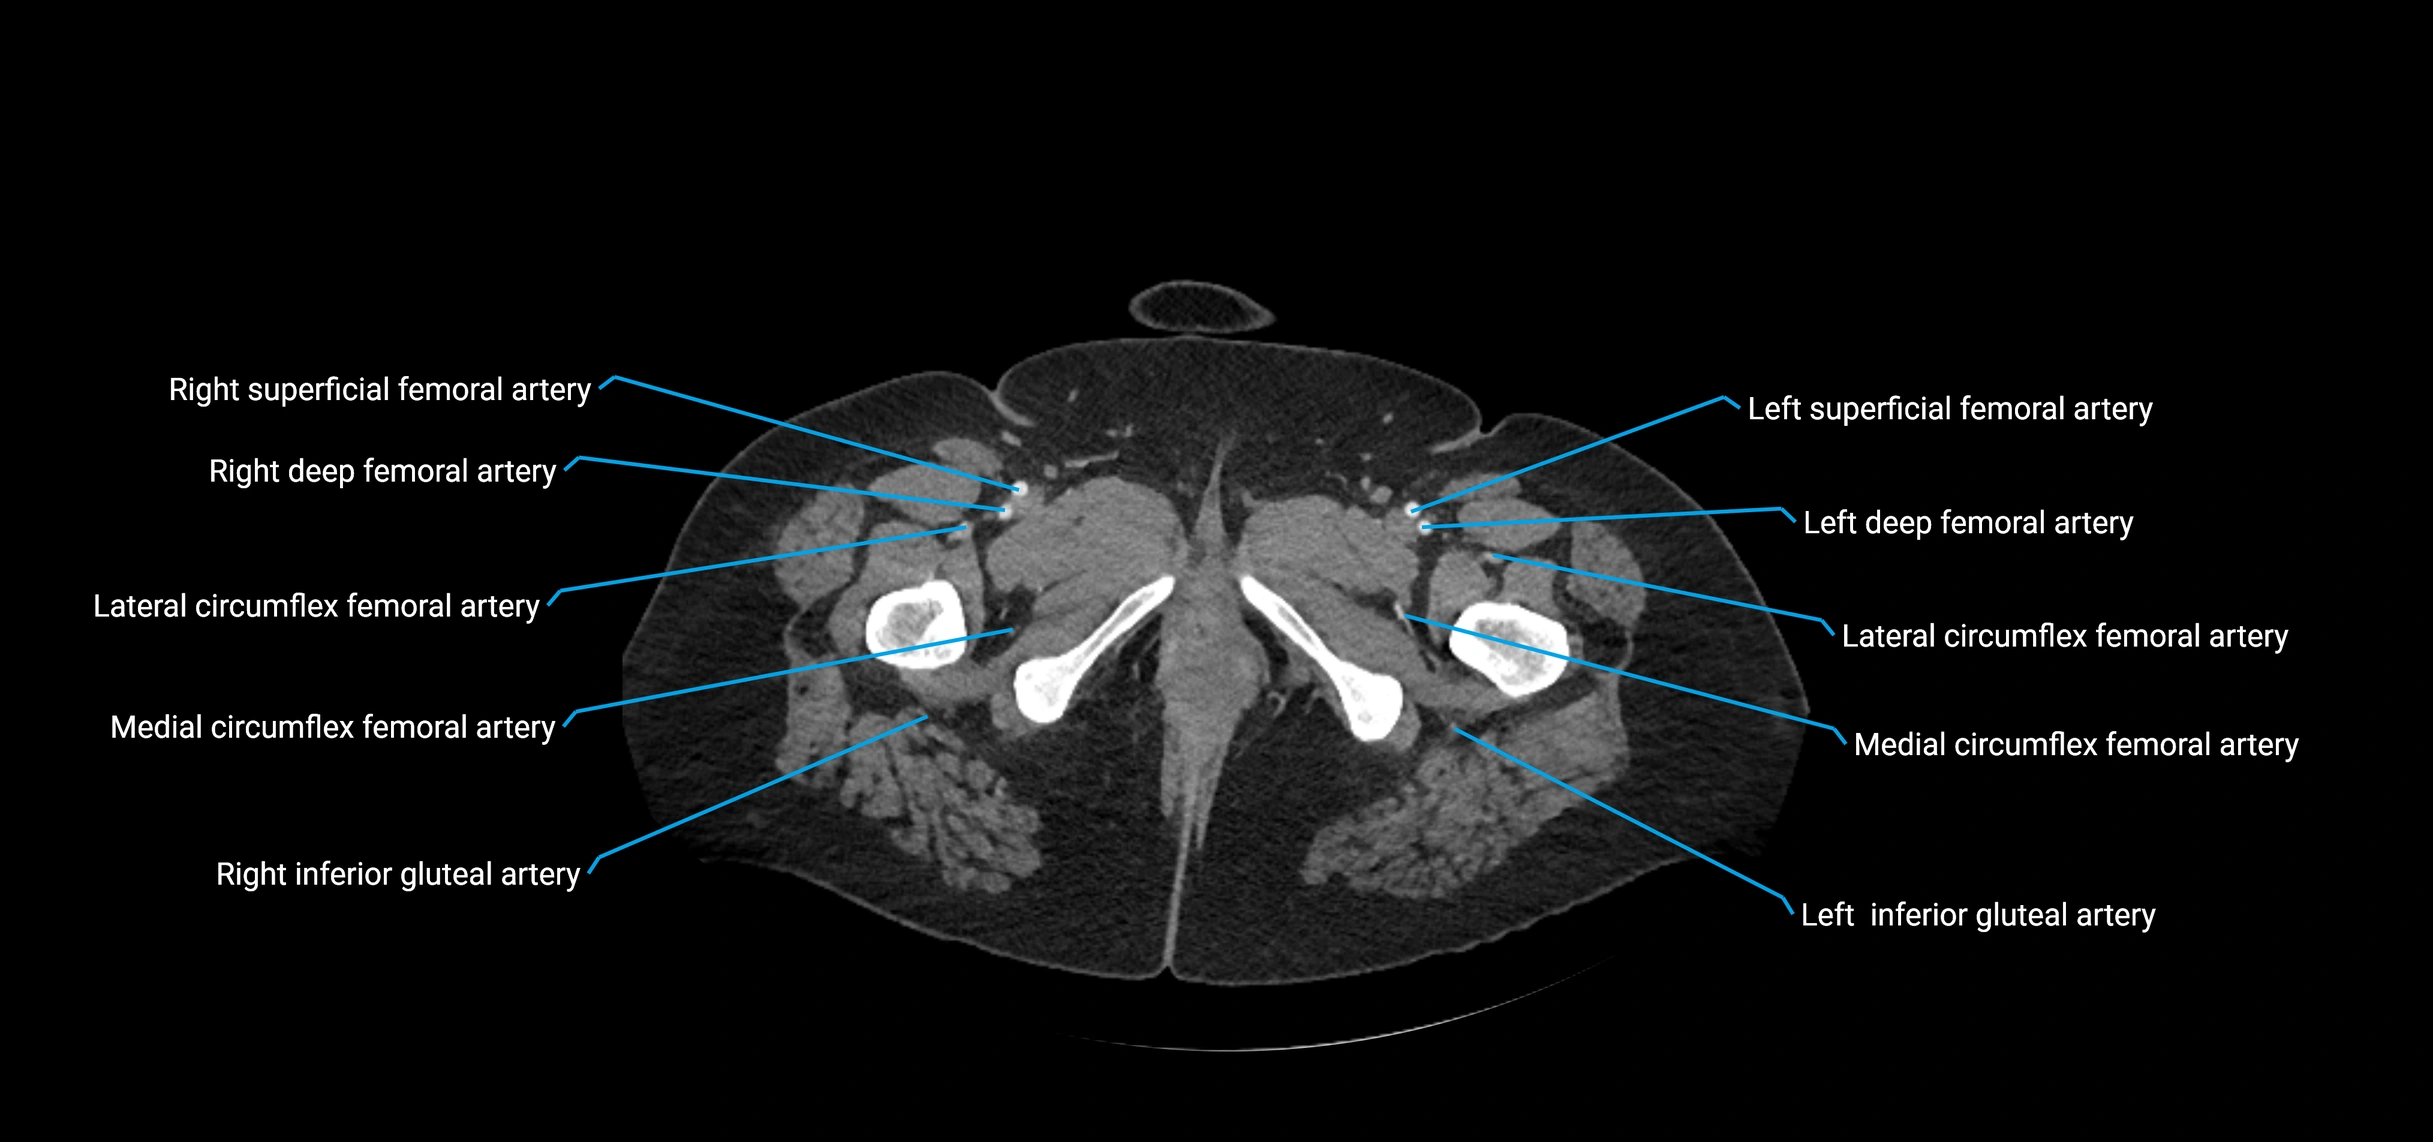

CT images

image

Contrast-enhanced CT (CTA):

• Gold standard for abdominal aortic imaging

• Provides excellent detail of lumen, wall, aneurysm, thrombus, and branch vessels

• Multiplanar and 3D reconstructions help in aneurysm measurement, stent graft planning, and dissection evaluation